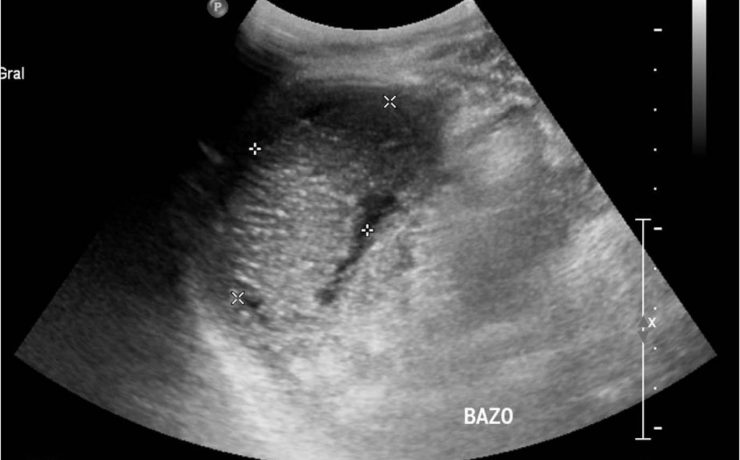

Patología fetal segundo trimestre

El RCIU constituye una de las mayores complicaciones del embarazo en. En incidencia de 3 a 10% en países desarrollados y 30% en países en vías de desarrollo. Recién nacidos con RCIU expuestos a riesgos de morbimortalidad neonatal por asfixia perinatal, encefalocele, hipoxia –isquémica, circulación fetal persistente, enterocolitis necrosante etc…